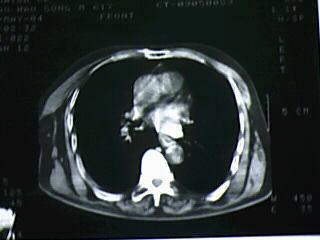

标题: CT19768:男 61岁 胸痛 咯血 一周。无发烧、无结核病史。 [打印本页]

标题: CT19768:男 61岁 胸痛 咯血 一周。无发烧、无结核病史。

右下肺中心型肺癌

右下肺支气管扩张

纵隔窗图像不佳,怀疑右下叶支气管有狭窄,来几张清楚的,暂考虑----感染性病变----抗炎后复查